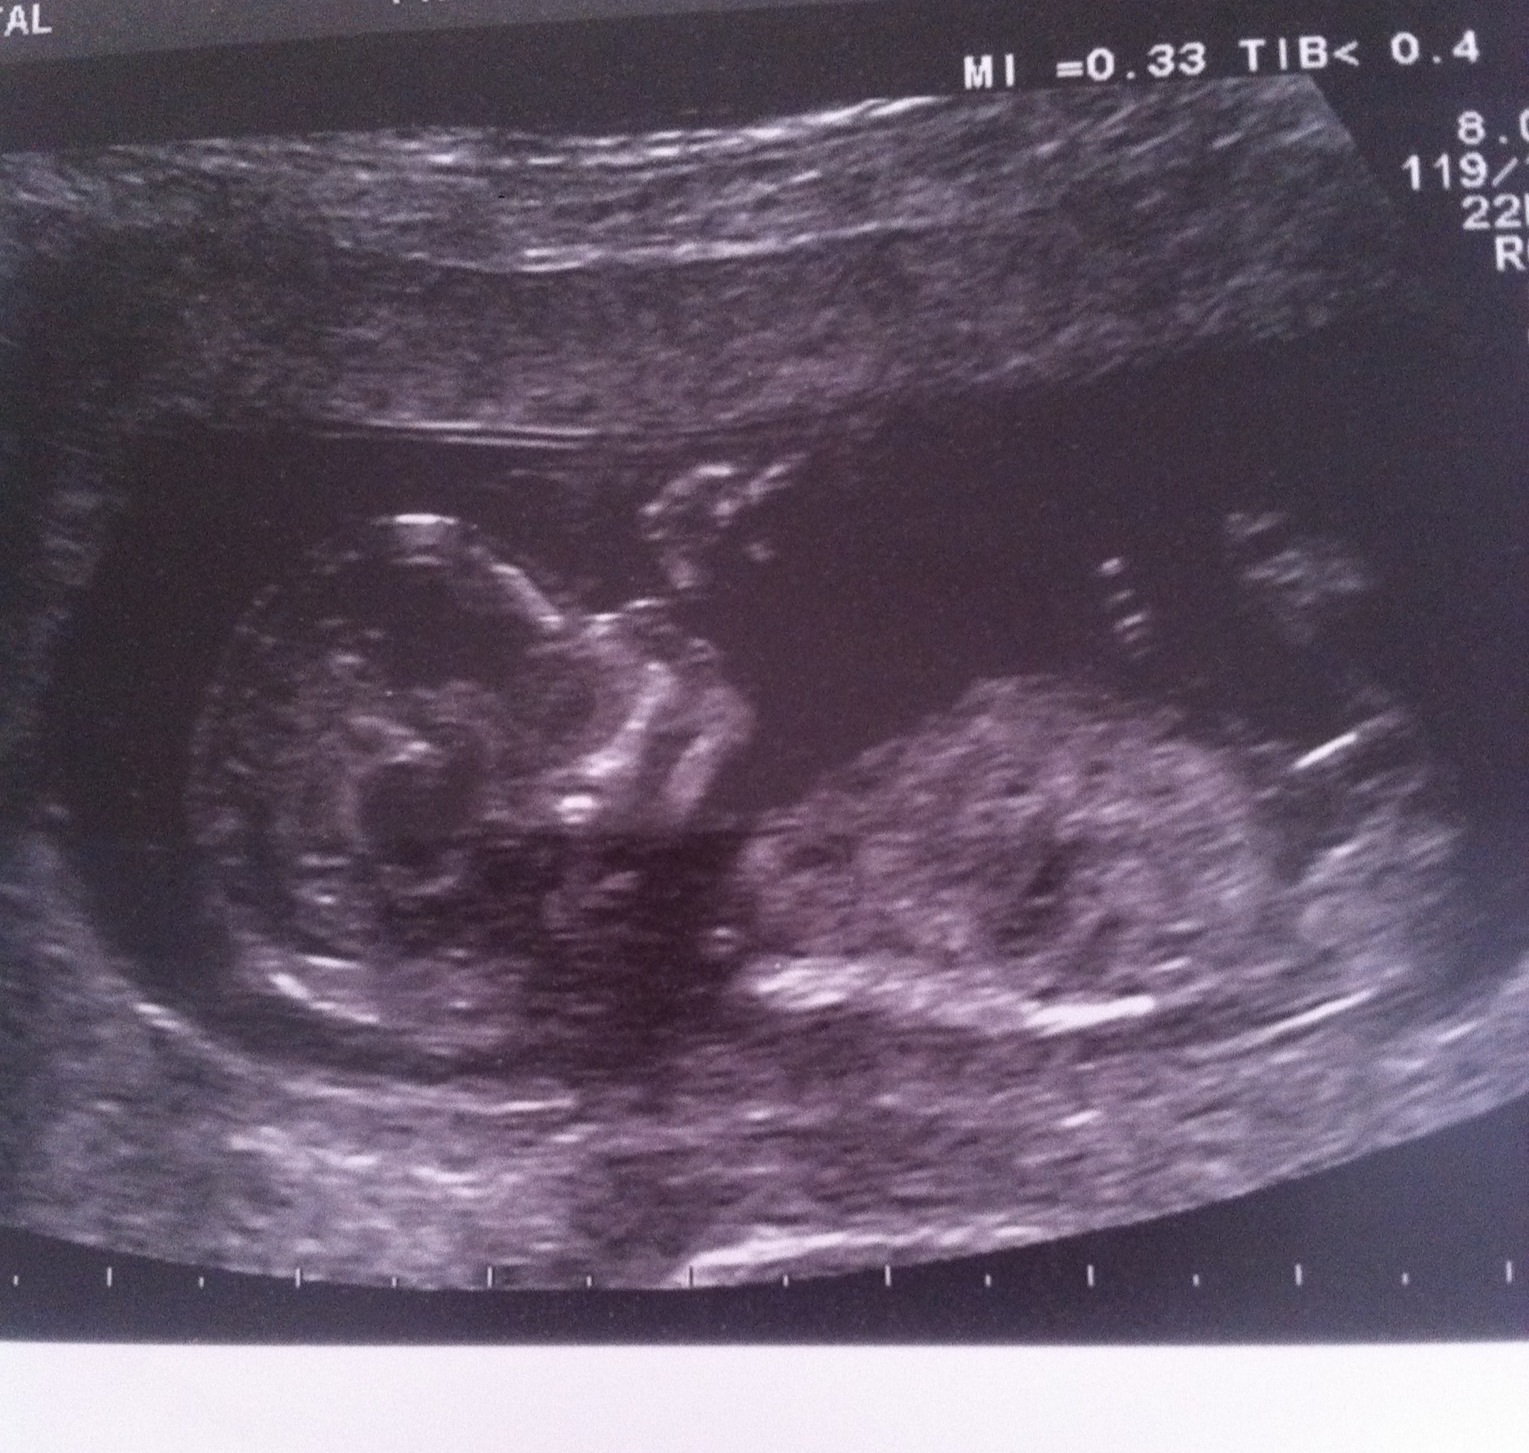

Thank you gender dreaming. My sway worked.Attachment 16386 Here are my ultrasound pics that are confirmed boy :).

20week 4 days